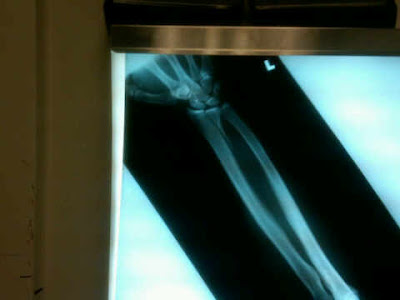

The x-ray above is Dan's wrist. It's broken. Really broken. Surgically-repair required broken. I wonder how many times a cyclist - driver collision has resulted in the driver receiving percutaneous pins?

Dan's accident didn't make the paper (despite the fact that the driver tried to flee the scene of the accident -- a crime he wasn't even ticketed for). No one was outraged. It passed into history without note, except by us.

We are all wishing Dan the best for surgery, and a speedy and uneventful convalescence.